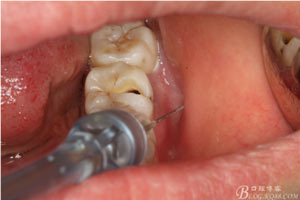

圖4.行下頜無(wú)痛阻滯麻醉